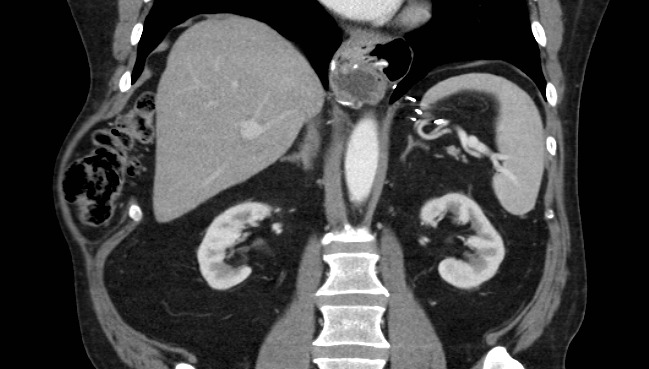

Patient #1 was initially diagnosed with a subcutaneous lipoma. Given the persistent nature, increasing size, and worsening symptoms from the bulge, a CT scan was performed to reveal a defect between anterior ribs 9-10 including cecum, ascending colon, and omental fat (Figure 1).